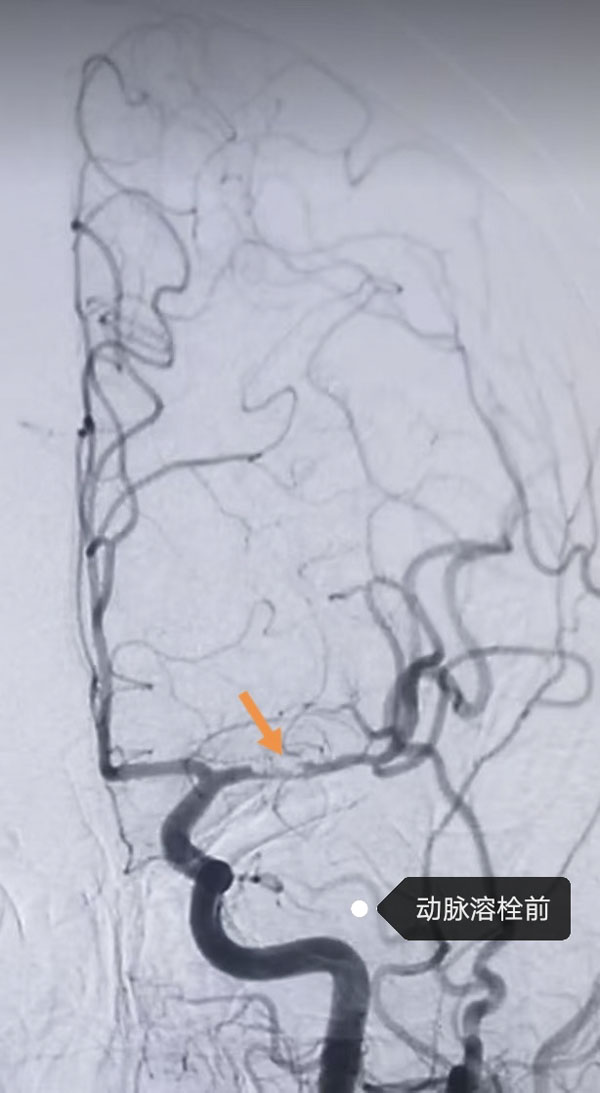

鉴于患者病情危急,接诊医生李晨曦紧急联系介入组李彦青医生启动卒中救治流程,在介入手术室的人员的帮助下,为其实施脑动脉造影术。术中,李彦青发现患者此次发病的责任血管“左侧大脑中动脉”虽存在血流再通,但局部仍为重度狭窄且血栓负荷重,遂决定通过左侧颈内动脉给药以改善局部血供。给药后,复查造影显示狭窄程度明显改善。术后,患者NIHSS评分(神经功能缺损评分)由入院时的8分快速降至3分,言语及右侧肢体活动不利明显改善。一周后出院时,评分进一步降至1分,言语及肢体活动基本恢复正常。